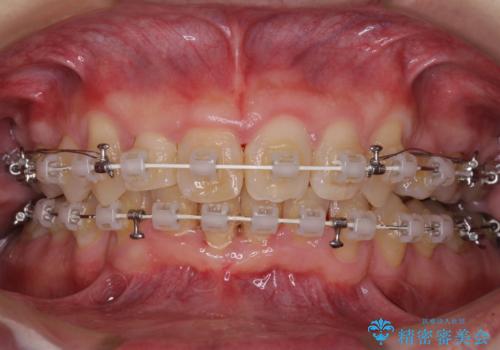

上顎歯列の叢生が著しかったため、上顎左右第一小臼歯2本を抜歯し、目立たないワイヤー装置にて治療を進めることとしました。

矯正治療後にはオーダーメイドタイプのオールセラミッククラウンを装着し、自然な口元に仕上がりました。